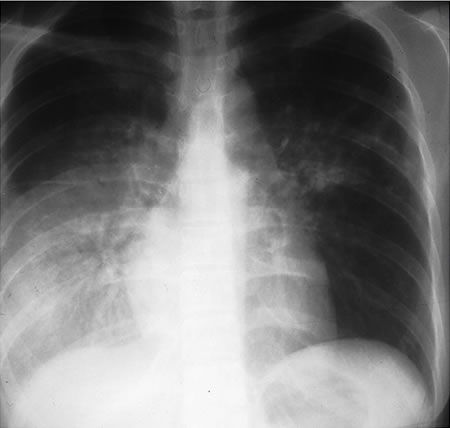

Is almost always abnormal in immunocompetent individuals. Typically presents as fibronodular opacities in upper lobes with or without cavitation. Atypical pattern includes opacities in middle or lower lobes, hilar or paratracheal lymphadenopathy, and/or pleural effusion.[Figure caption and citation for the preceding image starts]: Pulmonary TB with cavitationFrom the personal collection of David Horne and Masahiro Narita; used with permission [Citation ends].